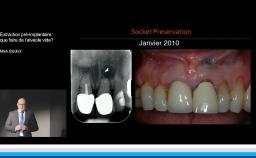

La présentation du Dr Rousseau reprend les choix auxquels est confronté le chirurgien-dentiste lors de la mise en place d’un implant dentaire.

De l’incision jusqu’aux sutures, le praticien fait face à une multitude d’options thérapeutiques qui conditionne la survie voire le succès de l’implant. La plupart des choix chirurgicaux repose sur la bonne compréhension des mécanismes biologiques de la cicatrisation et de l’homéostasie. Comprendre ces mécanismes, c’est orienter ses choix chirurgicaux vers un exercice raisonné de l’implantologie et accroître ses chances de succès.